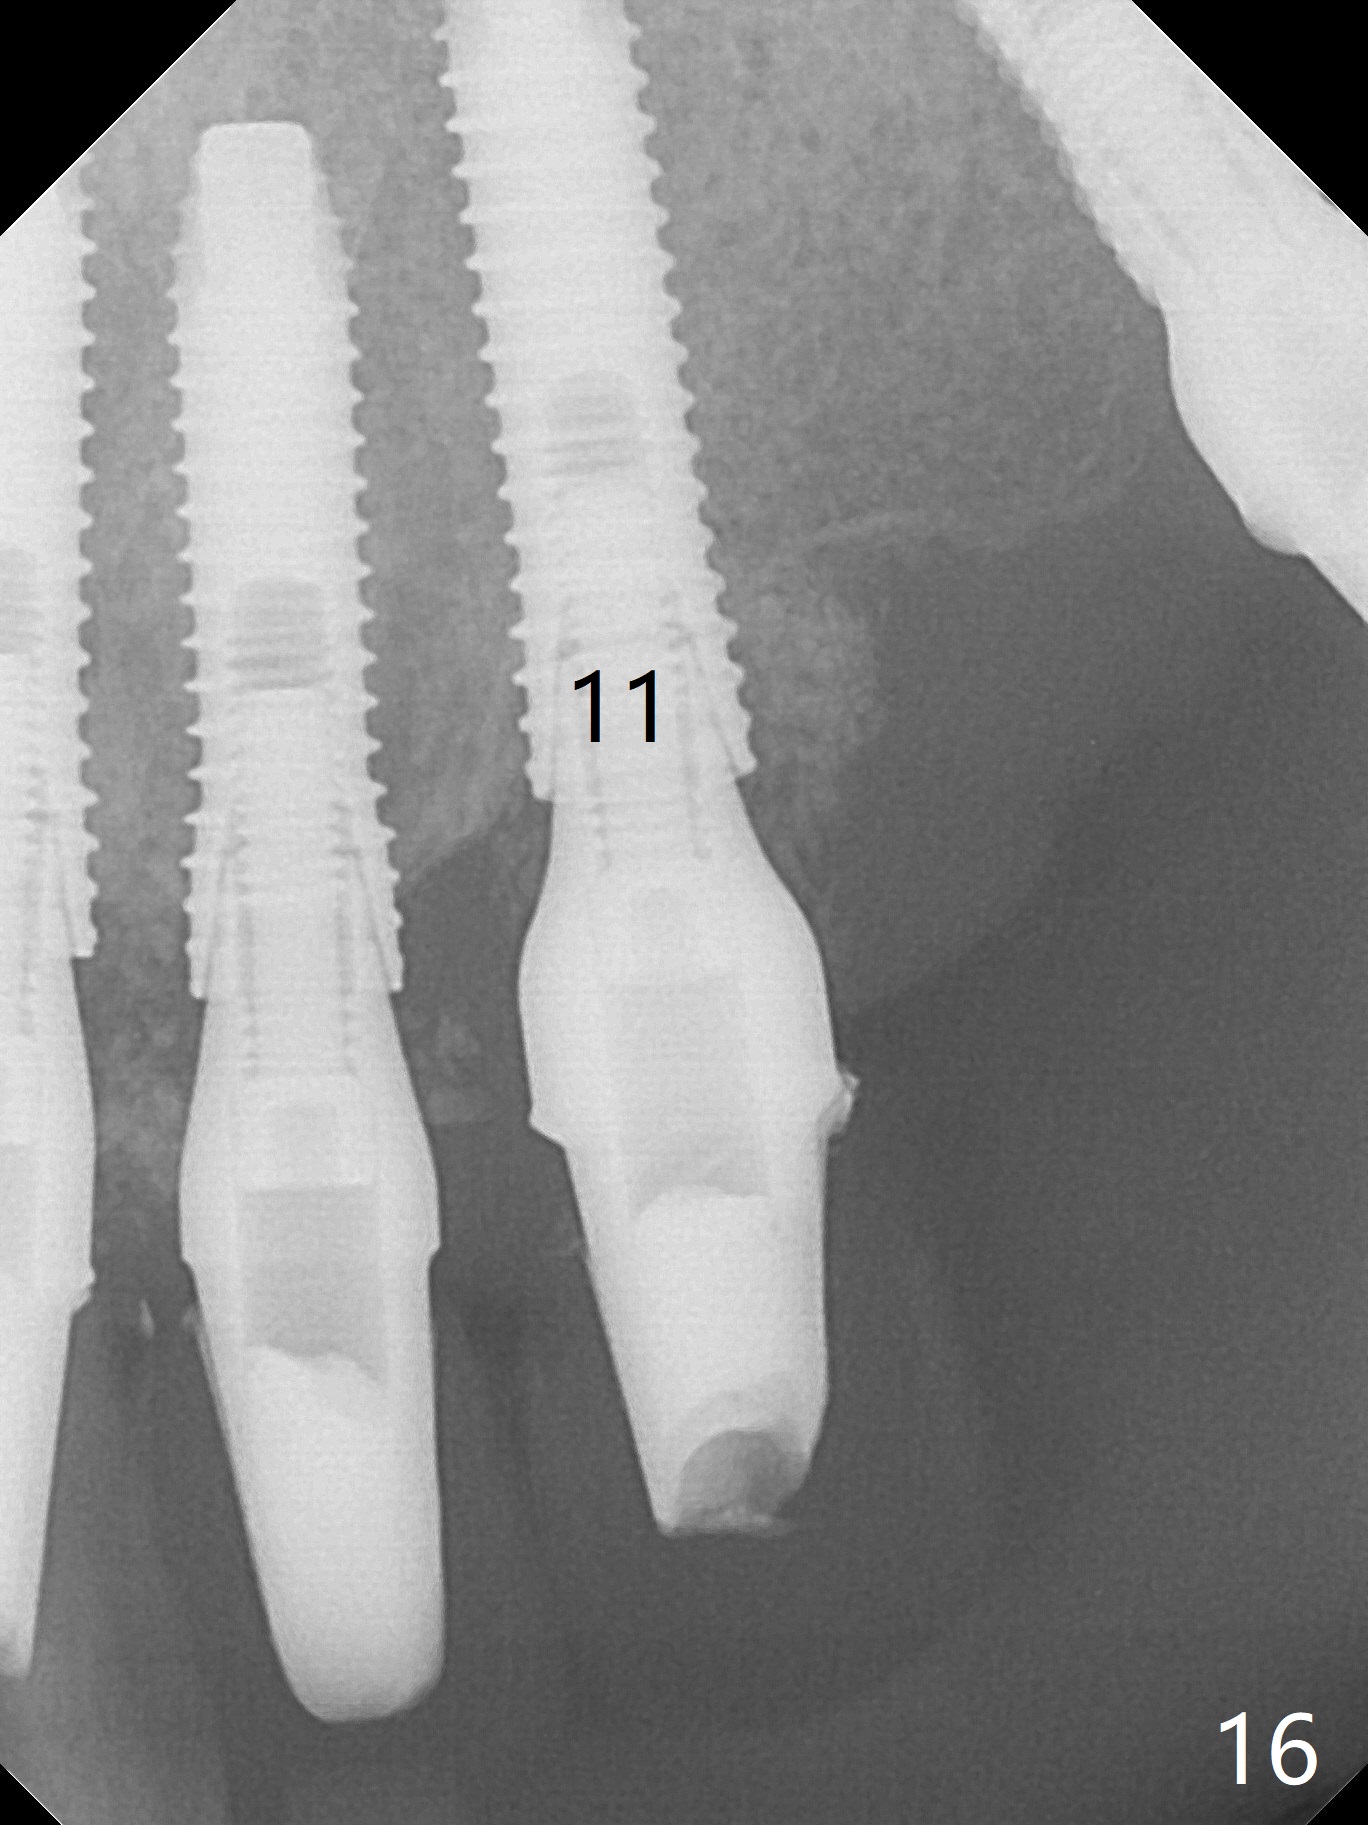

The patient returns 8 days postop, uncomfortable with overhang in the provisional (Fig.10 *). The sockets appear to be healing with loose bone graft (Fig.11) when the provisional is removed for trimming (Fig.12). Six (for #7,13) and seven (#9-11,15) months postop, the soft (Fig.13,17) and hard (Fig.14-16,18) tissues heal. It appears that the trajectory at #9,11 and 13 should be changed by using angled abutments (Fig.18,19 (panoramic X-ray taken 2 months earlier)) before provisional and final restoration.

There is 1-2 thread exposure mesial and distal at #10 two years postop (Fig.20'), which may be related to the small fistula labially (Fig.20 >). It appears that the implant at #10 was placed too high (Fig.21) and labially (Fig.22). In fact the bridge fractures between #12 and 13 during pandemic.